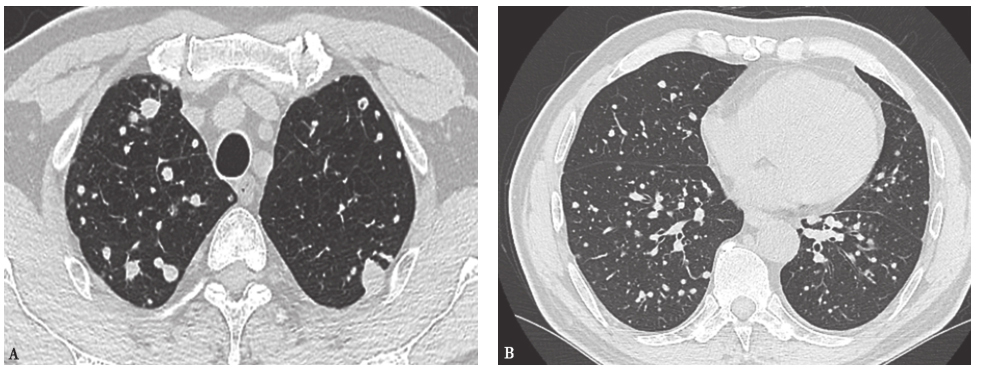

17个月前胸部CT见双肺弥漫性小结节(图1)。

图1 17个月前胸部CT表现